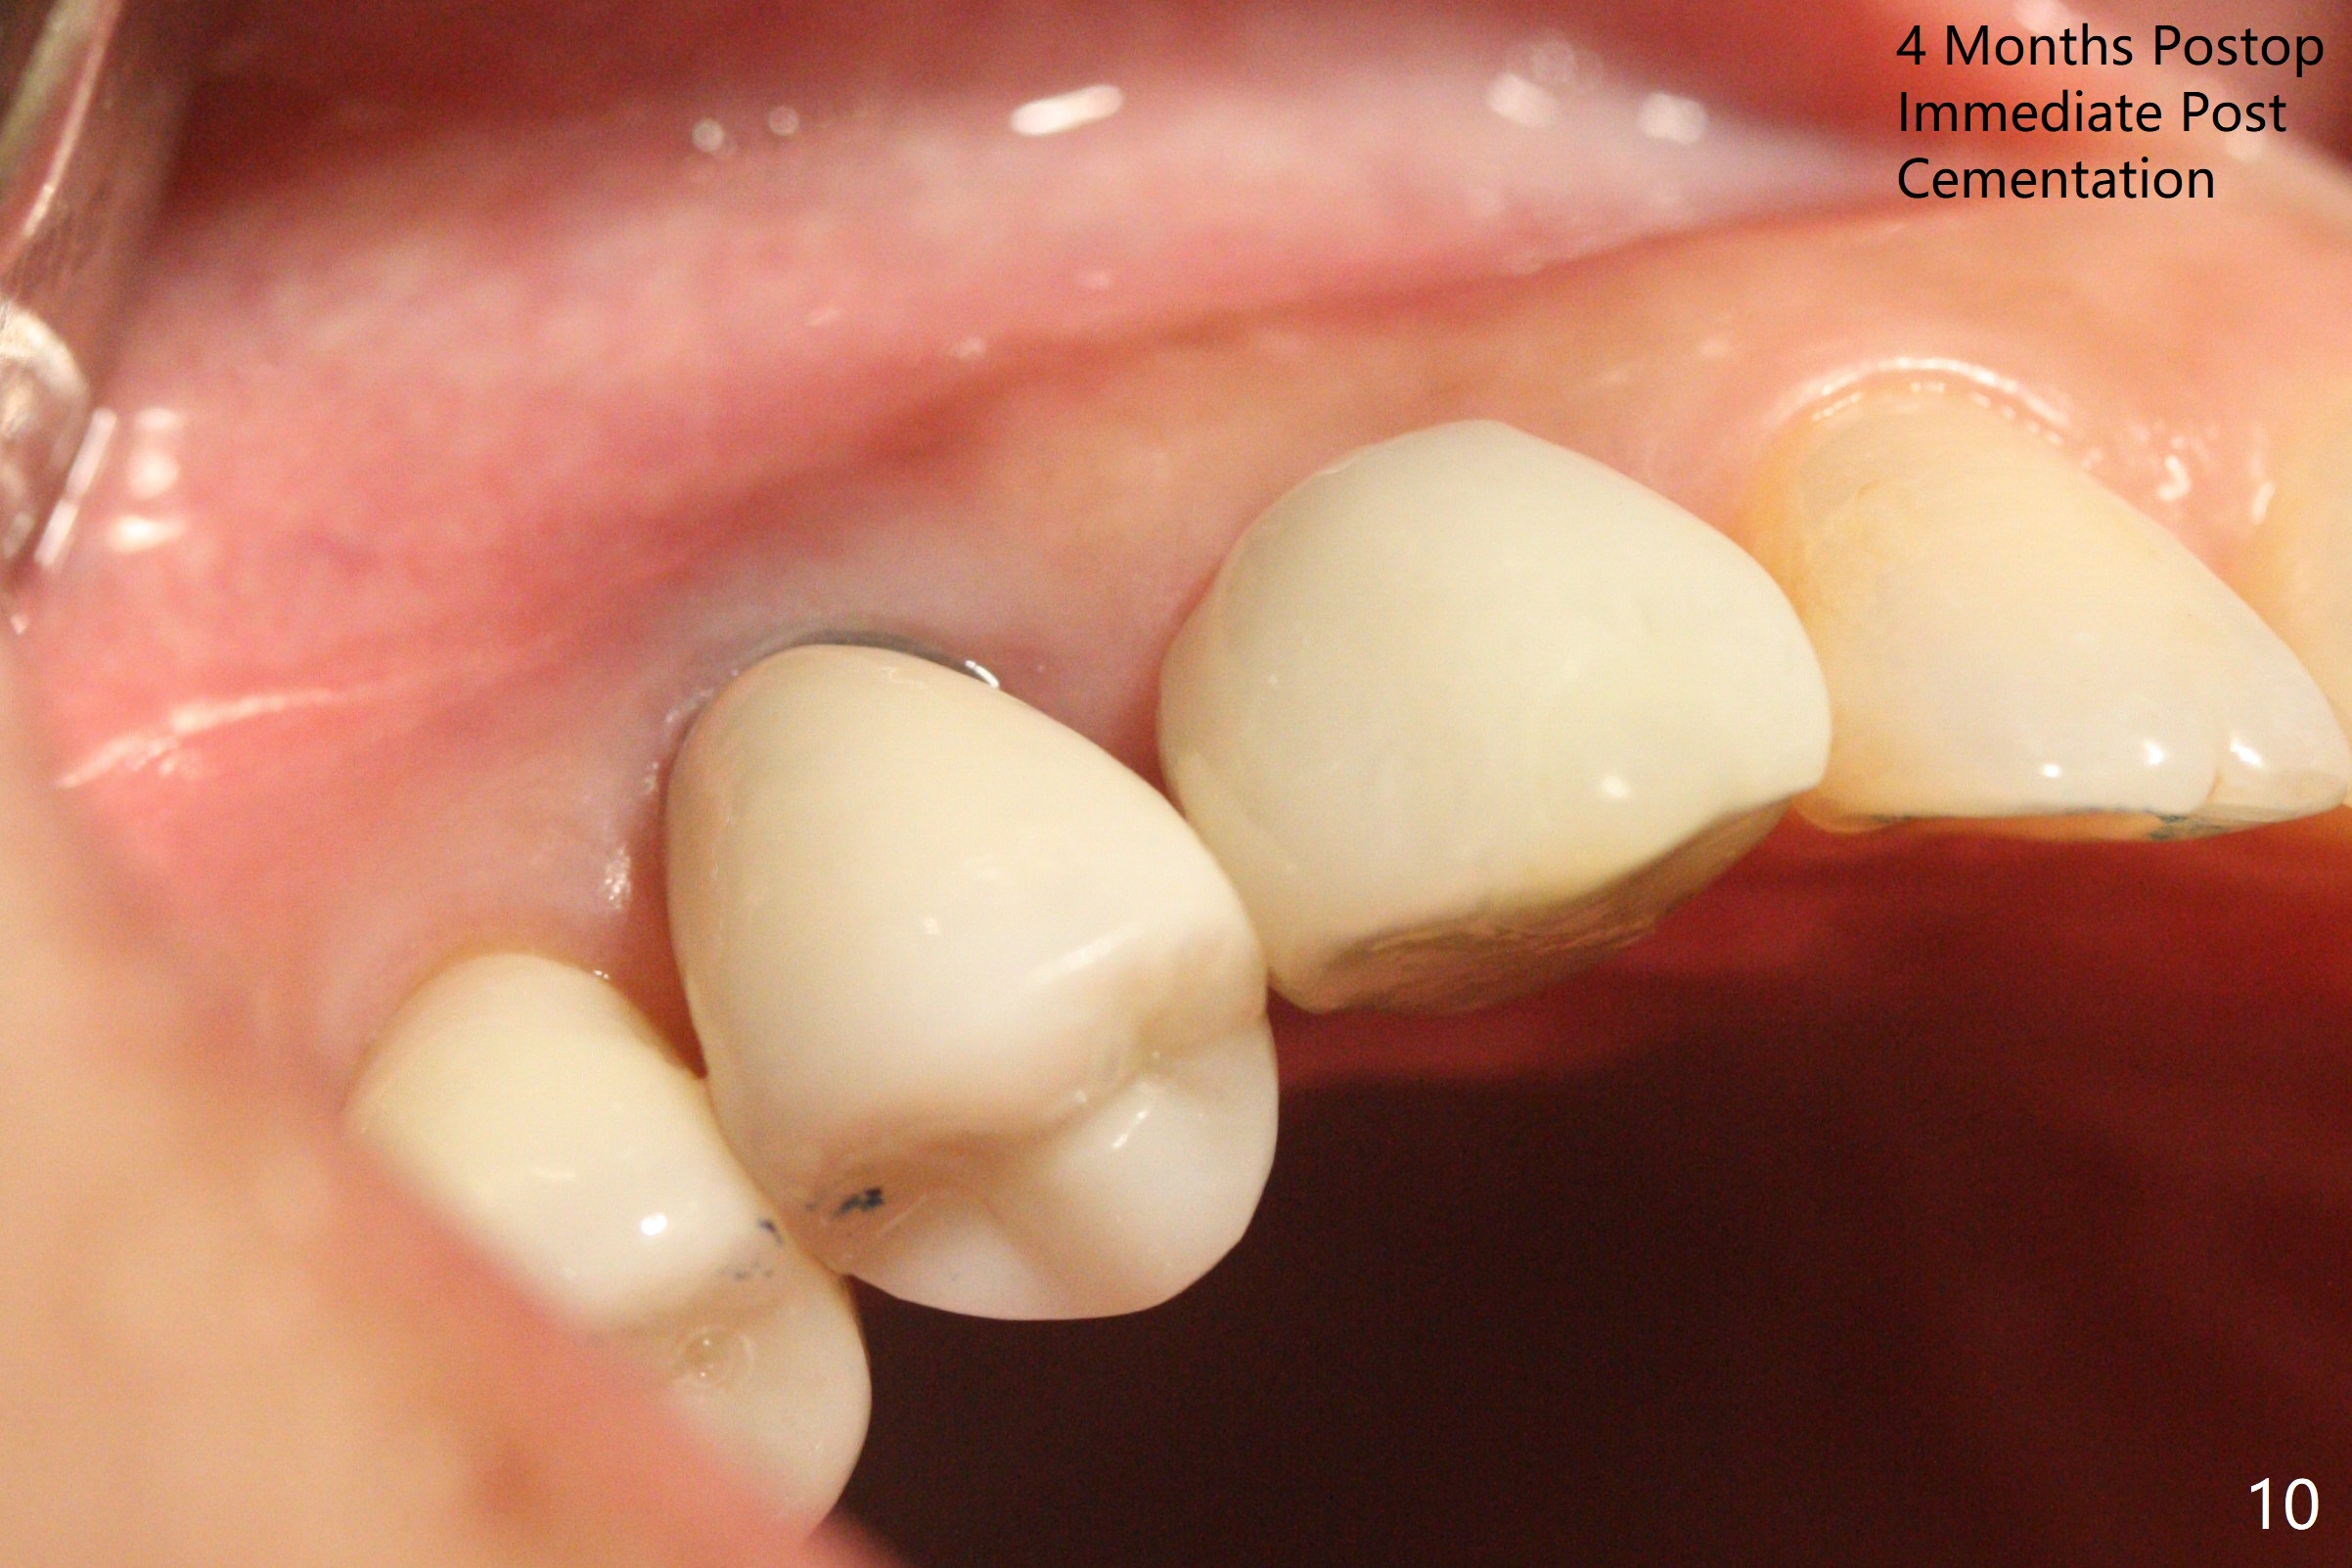

When the recemented crown at #6 is removed, the post is found to have been fractured. When the tooth is extracted, the socket walls are found intact. After moving the initial osteotomy (Fig.1) mesial, a 3.8x13 mm implant is placed (Fig.2). Clinically it appears supracrestal lingually. So the implant is placed deeper, but a cemented abutment is incompletely seated (Fig.3 <). When a longer abutment is used (easy grasping), it is seated completely (Fig.4). Then sticky bone is packed (Fig.5 *). When an immediate provisional is fabricated and seated, PRF membranes are inserted into the remaining gap between the gingiva and the provisional. Free hand surgery takes time and more intraop X-ray. It is inconvenient with nervous patients. The socket heals 2 weeks postop (Fig.6). The provisional will be next relined and reseated. It is difficult to insert gingival retraction cord 3.5 months postop because of the deep mesial margin. When an abutment with longer cuff is placed, the packing is easier (no biologic width violation, Fig.7 (^: resorbed mesial crest), as compared to Fig.5). When the crown is cemented (un-esthetic due to failure of use of temporary abutment), the metal shows at #5 with gingival recession because of buccal placement (Fig.8-10). Bone resorption is severe between #5 and 6 (Fig.7), as related to large gingival embrasure (Fig.9 *). When #5 crow is redone, move the gingival margin apical and fabricate provisional.